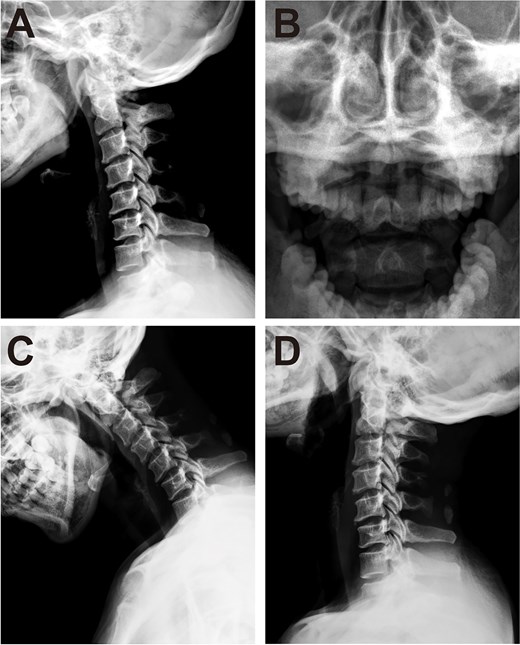

Cervical radiographs revealed hypoplasia of C1 but no evidence of atlantoaxial dislocation (Fig. 1). CT scans indicated bilateral bone abnormalities on the lateral sides of the posterior arch, particularly on the left side, with a midline cleft of the anterior arch (Fig. 2A). Three-dimensional reconstruction further demonstrated this abnormality (Fig. 2B–D). T2-weighted MRI revealed an intramedullary high signal at the C1 level, but no compression of the cord was observed (Fig. 3A and B). Cervical flexion-extension imaging indicated minor stenosis of the upper cervical spinal cord in the neck flexion position, but this alteration was not substantial (Fig. 3C–F). We considered that the high signal may be related to the repeated subtle activity of the posterior atlantoaxial arch in the past over a long period of time.

Cervical CT scan. (A) Axial CT image showing hypoplasia of the posterior arch and midline cleft of the anterior arch. (B–D) Three-dimensional reconstructed CT images showing atlas deformity from different views.